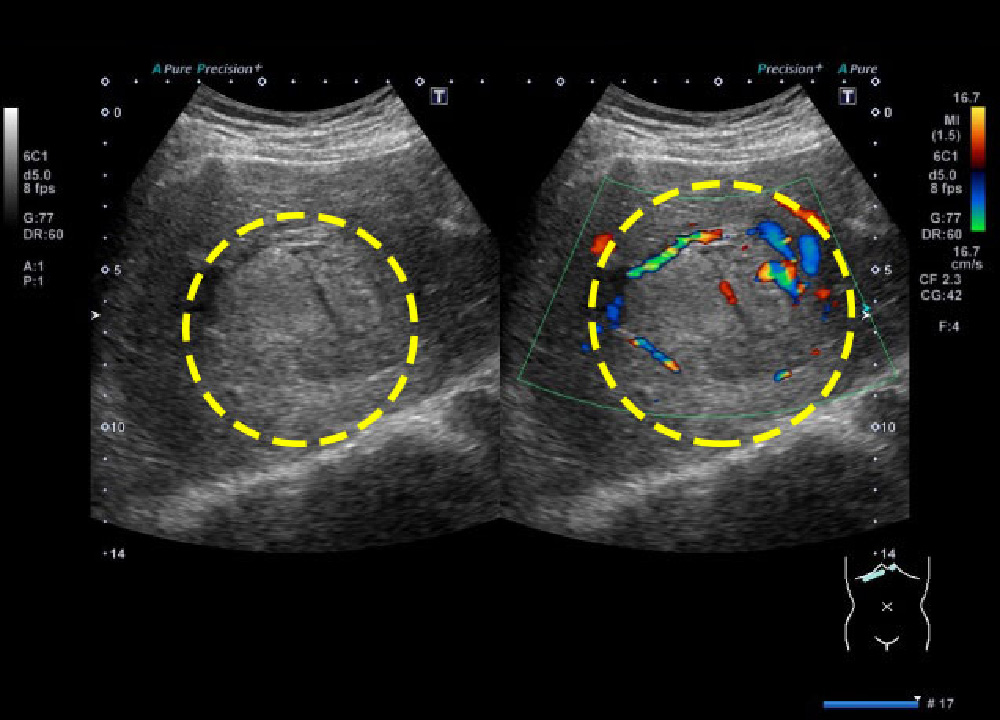

フィリップス、「Liver Fat Quantification(肝脂肪化定量評価。肝臓がん|消化器|診療内容|医療法人 甘木第一クリニック。肝臓がん|消化器|診療内容|医療法人 甘木第一クリニック。sakuraさん専用 蔵王吊るし柿4kg 紅干し柿 600g。Contrast Enhanced Ultrasound (CEUS) | フィリップスヘルスケア。Liver Ultrasonography | SpringerLink。キヤノンメディカルシステムズ、『肝臓の脂肪量の汎用超音波画像。Imaging Features of Hepatocellular Carcinoma in the Non。Imaging Features of Hepatocellular Carcinoma in the Non。714cFtk9QyL._AC_UF350,。肝臓病変における超音波の最新情報-第24回腹部放射線研究会。KMS_M01_XXX_670.jpg。腹部の超音波検査健康なヒト胆嚢 - 胆嚢のストックフォトや画像。